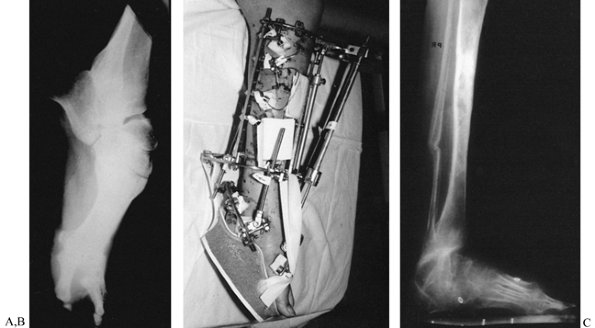

![]() |

Figure 32.35. A,B:

Translational deformity may also be seen in two planes. This tibial nonunion has a posterior and lateral translational deformity. C: The posterior translation measures 2 cm, while the lateral translation measures 2.7 cm. When these are plotted on a graph, it demonstrates that the true translation is 33 mm in a plane oriented 36° to the frontal plane. This graph is drawn as for a right leg. |